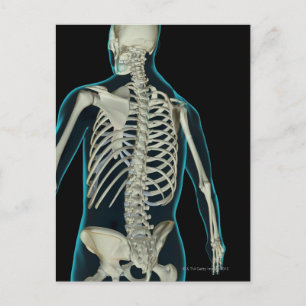

Impressão Em Tela ideia 3D do sistema respiratório fêmea 1

PreçoR$ 435,00

Produto oficialmente licenciado